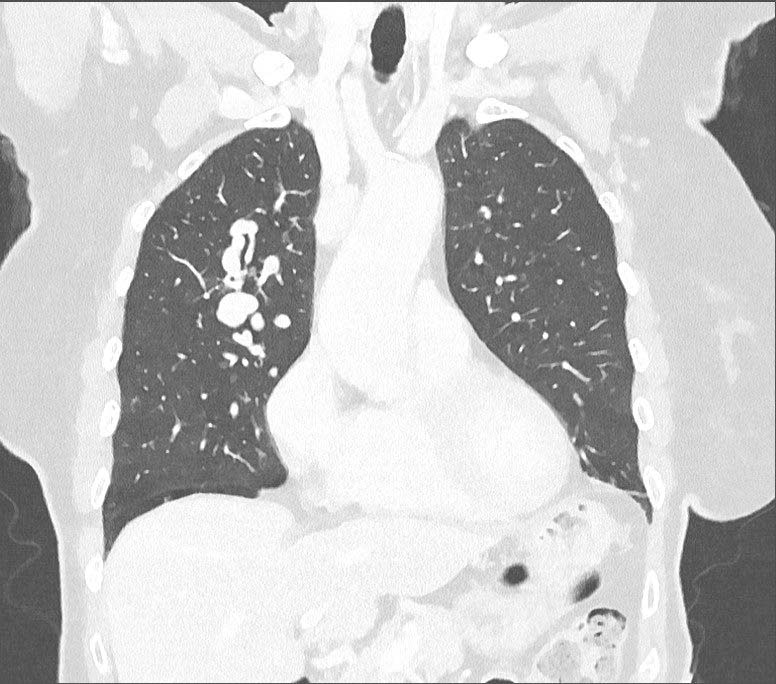

Haar huisarts verwijst haar naar de Eerste Harthulp, waar de uitslag van het bloedonderzoek (troponine en d-dimeer) normaal blijkt te zijn, afgezien van een hypoxemie (pO2 58 mmHg; normaal 75-100 mmHg). Op de thoraxfoto zijn verdichtingen te zien [figuur 1], die na hogeresolutiecomputertomografie op pulmonale arterioveneuze malformaties blijken te berusten [figuur 2]. Er is tevens sprake van een forse rechts-links shunt. De patiënte geeft aan vaak bloedneuzen te hebben, net als haar jongere broer. Een oudere broer blijkt vroeger geopereerd te zijn aan een pulmonale malformatie.

Hogeresolutiecomputertomografie-thorax: pulmonale arterioveneuze malformaties in de rechter long

Figuur 2 | Hogeresolutie-computertomografe-thorax: pulmonale arterioveneuze malformaties in de rechter long